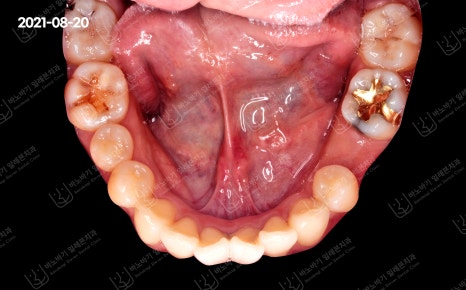

악궁 모양도 좀 더 이상적인 U자형 아치로 완성됐습니다. 추가적인 조치를 요하지 않아 고정성 유지장치를 부착하여 교정을 마무리하였습니다.